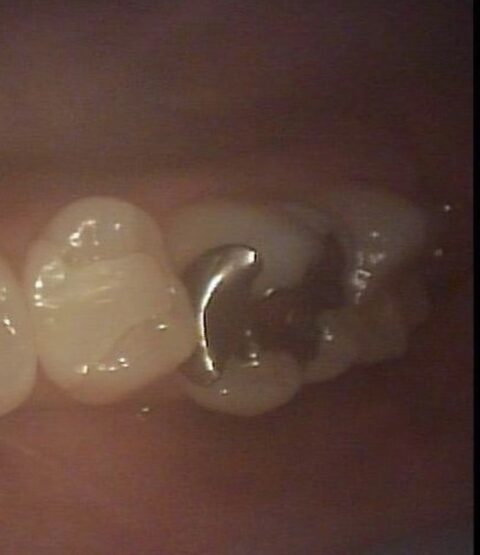

本日は銀歯が嫌でセラミック治療を希望された患者様の症例です。

一見、綺麗に銀歯が入っているように見えますね。

銀歯を外してみると、縁や内部で虫歯が発生しています。

■健康保険適応の銀歯は安価ですが、お痛みは出ていなくても数年経つと隙間等が生じ、内部で虫歯が進行してまうケースが多くあります。